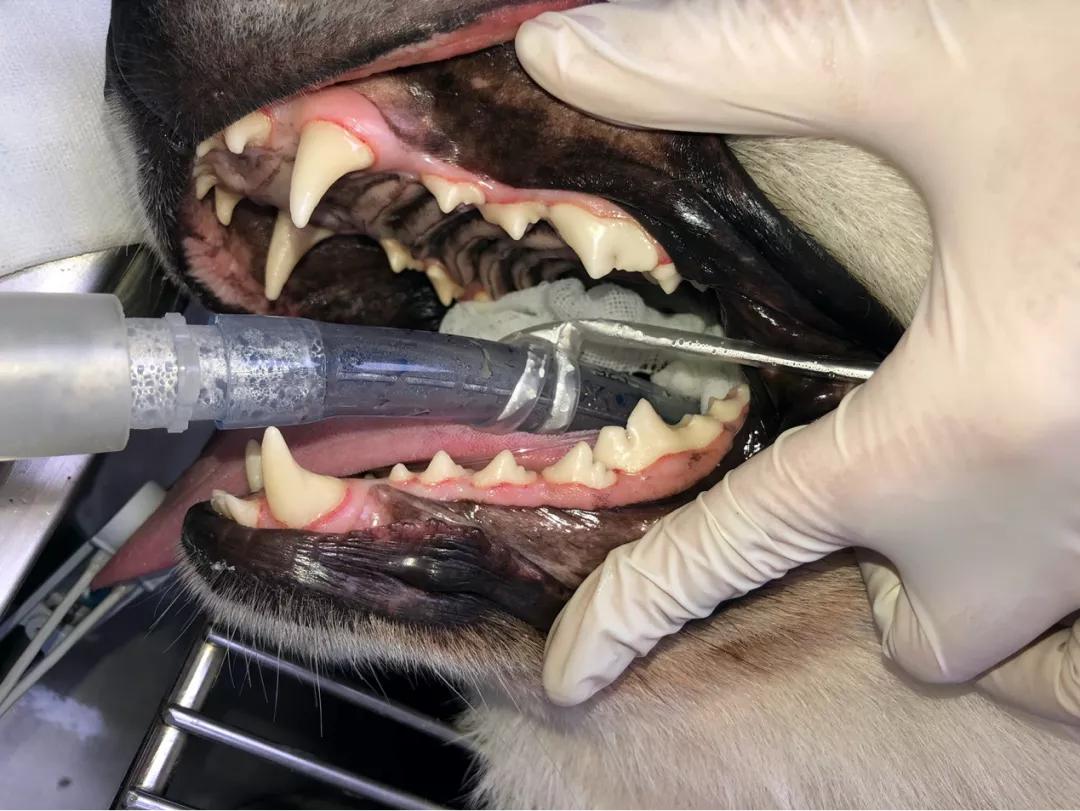

彭医生先是仔细观察了汪兄汪弟的牙齿,发现兄弟俩除了牙黄、牙脆、口臭,还有 大量牙结石、并且有牙龈炎等情况 。

(彭医生看牙中,可以看到牙齿黄黄的)

在这之前,要 先评估牙齿状态 ,彭医生为俩狗狗用 牙科探针 检查待修复牙釉质的面积、检查是否有牙龈炎等症状。

(彭医生做DR检查时的场景)